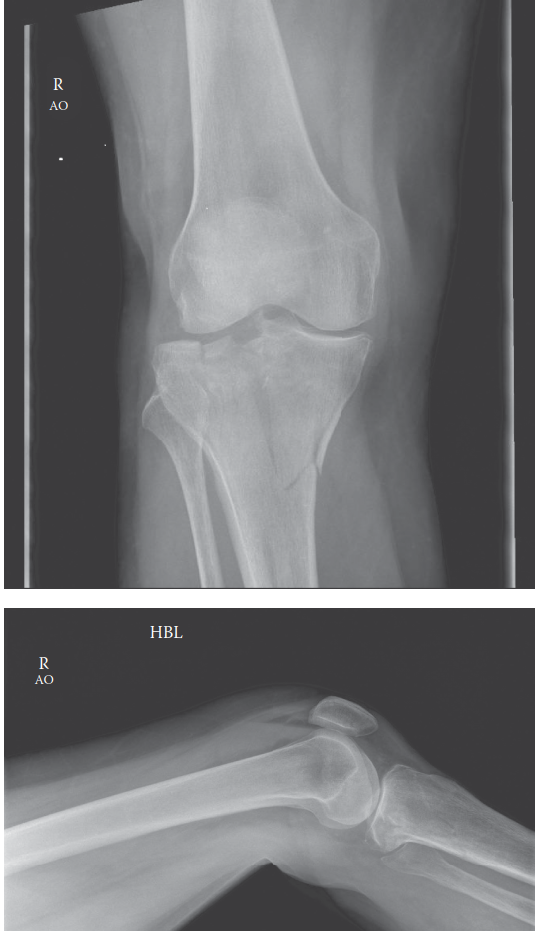

These are the radiographs for a patient involved in a high-energy road traffic accident. Describe the appeara…